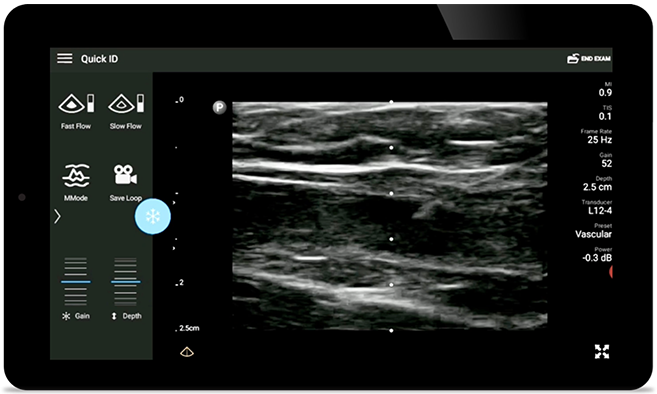

Уменьшение количества осложнений при катетеризации центральных вен

Ультразвуковое сопровождение в реальном времени может повысить точность и безопасность катетеризации центральных вен.

• Расширенный диапазон рабочих частот — от 12 до 4 МГц. • Размер апертуры: 34 мм. • 2D, управляемый цветной доплеровский режим, M-режим, продвинутая визуализация XRES и многомерная гармоническая визуализация, SonoCT. • Визуализация с высоким разрешением для исследования неглубоких структур: мягких тканей, сосудов, поверхностных тканей, костно-мышечной системы и легких. • Маркер центральной линии. • Датчик USB-C со сменным кабелем.